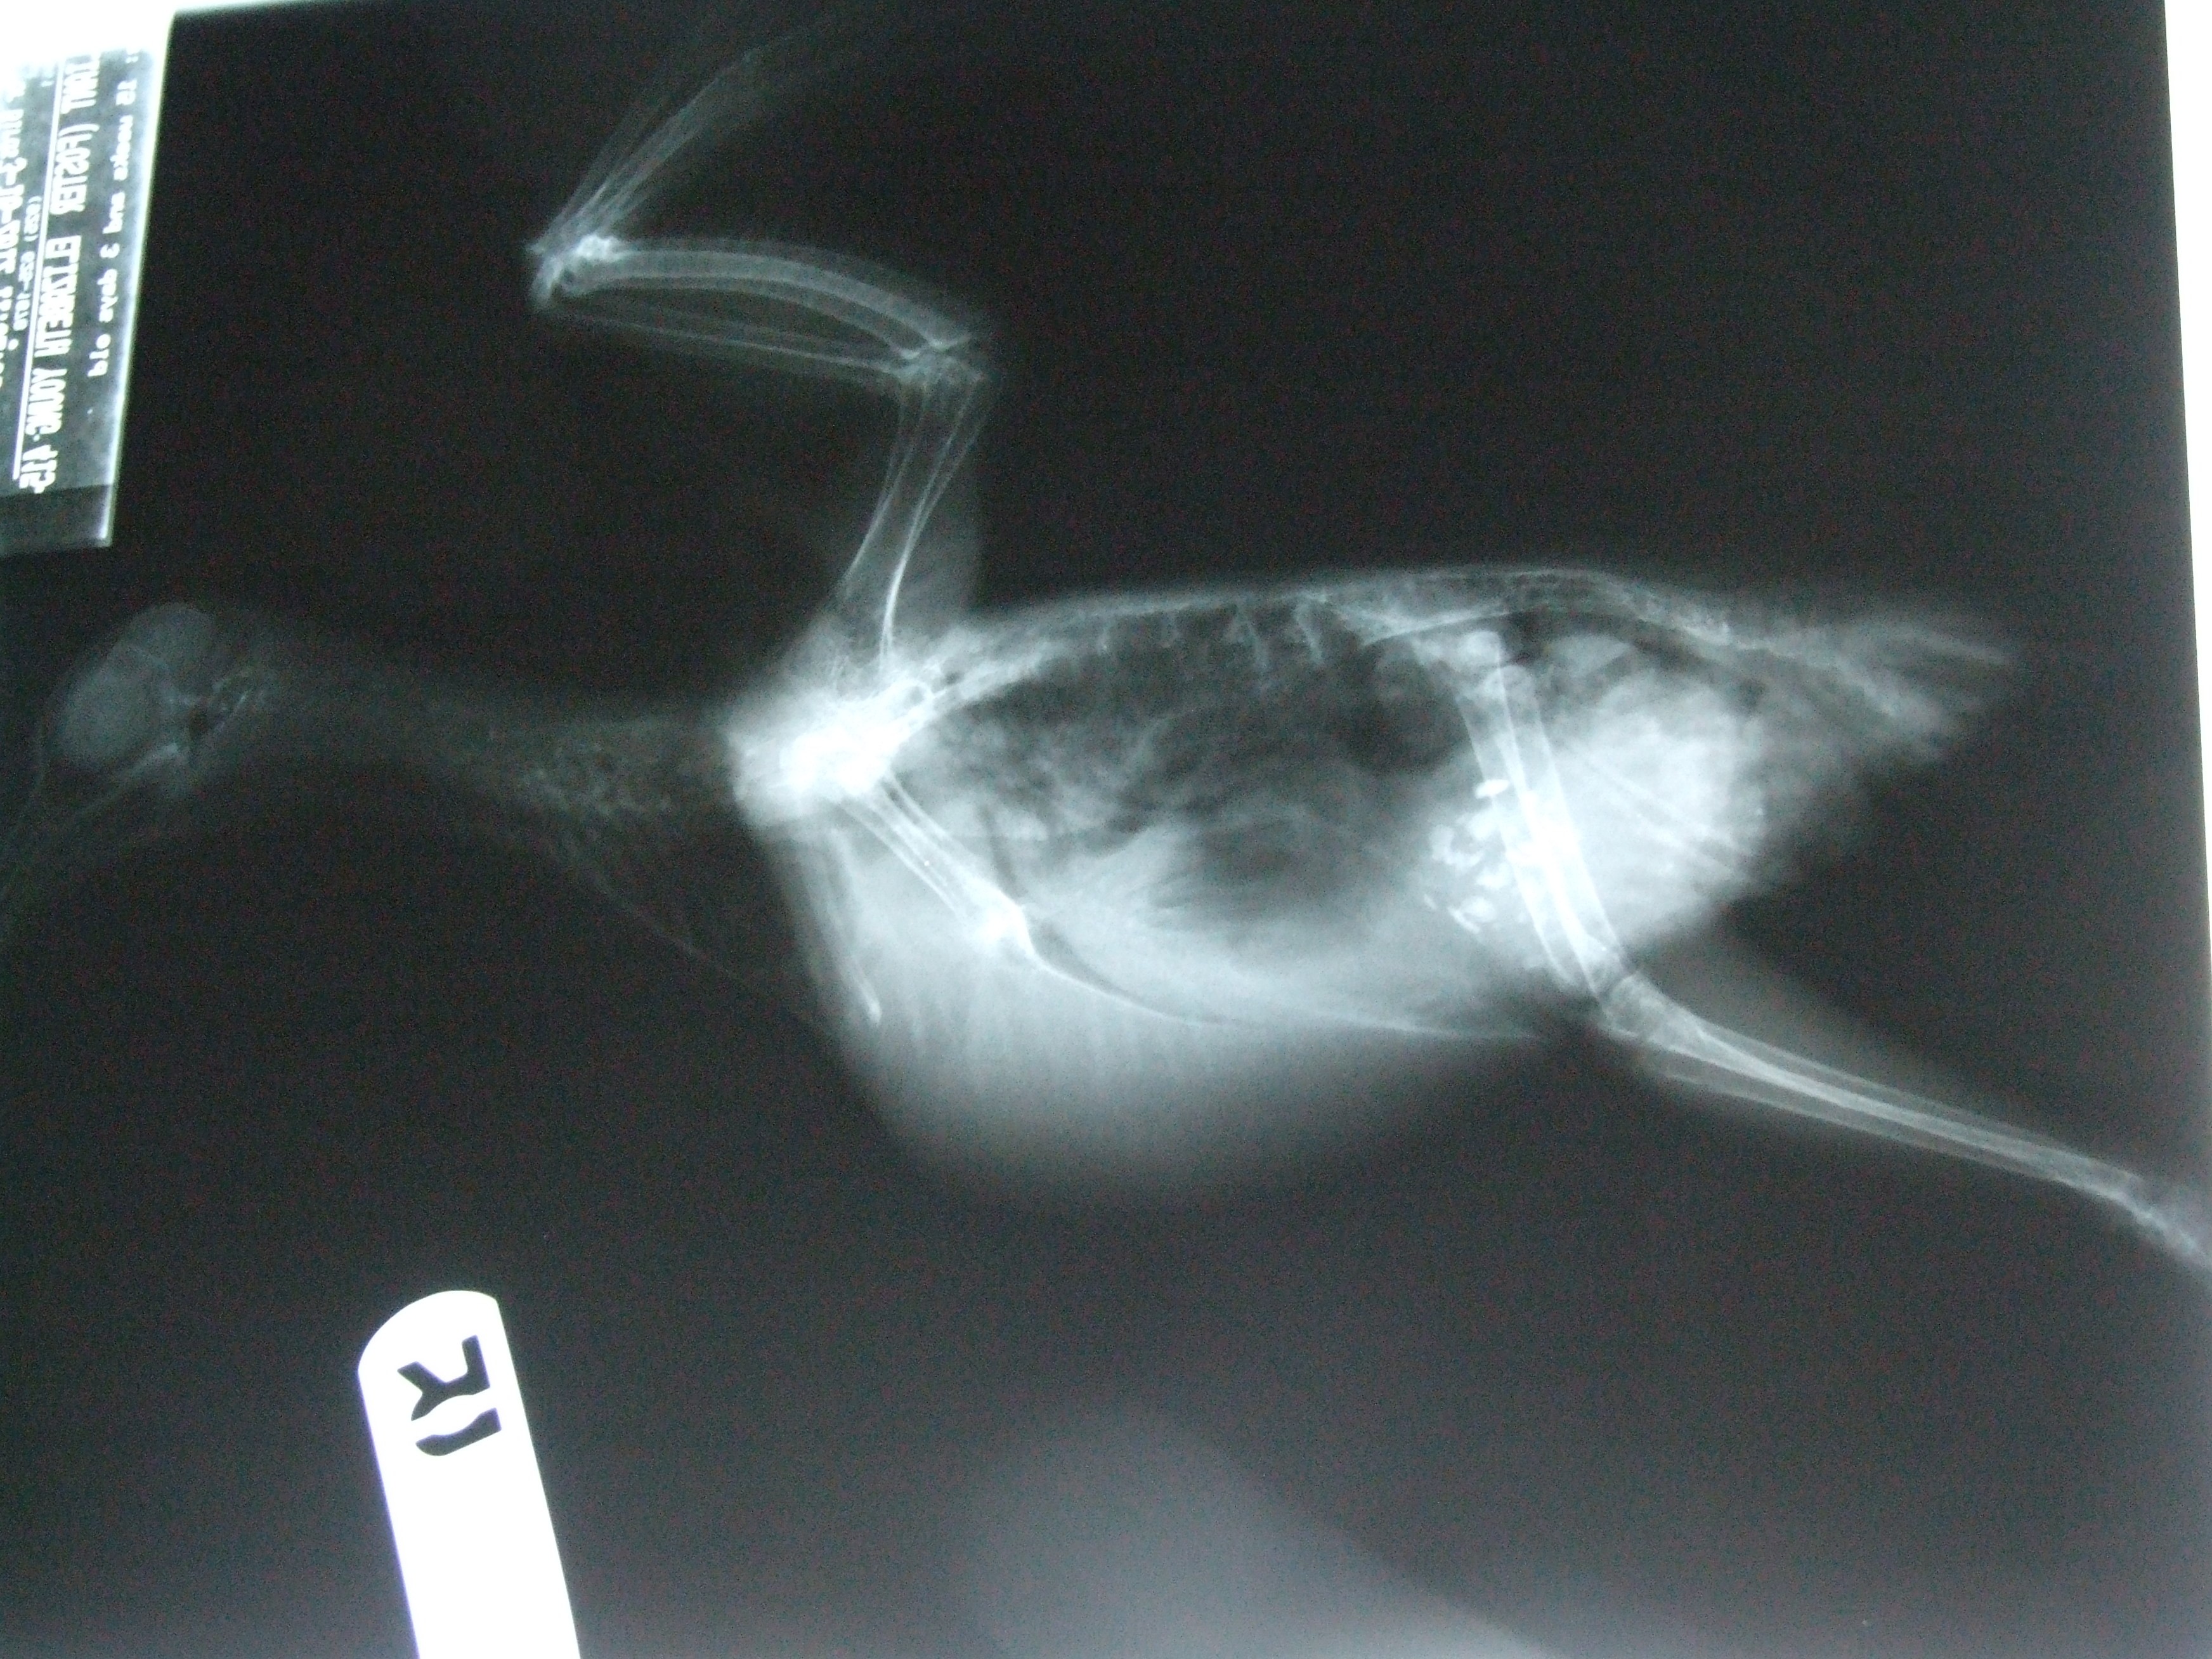

Pigeon Chest X Ray Pigeon Chest Respiratory (gosh) explains the causes, symptoms and. pectus carinatum (pigeon chest) refers to a chest wall deformity in which the sternum protrudes anteriorly. pectus carinatum (pigeon chest) is a deformity of the chest wall in which the breastbone and ribs are pushed outward. Pectus carinatum, sometimes called pigeon. this page explains the common causes, symptoms, diagnosis and treatment. Pigeon Chest Respiratory.